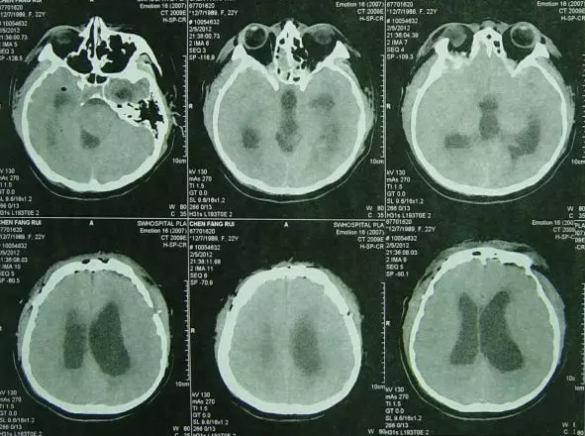

出院后2年余即2014年11月15日,通过微信传来在当地医院做的头部影像检查示未见异常(图-13),自述身体一切正常。

图-13:2014年11月15日头部影像

出院后4年零7个月即2017年4月5日,通过微信传来在当地医院做的头MRI检查示未见异常(图-14),自述工作和生活正常。

图-14:2017年4月5日头MRI(完)